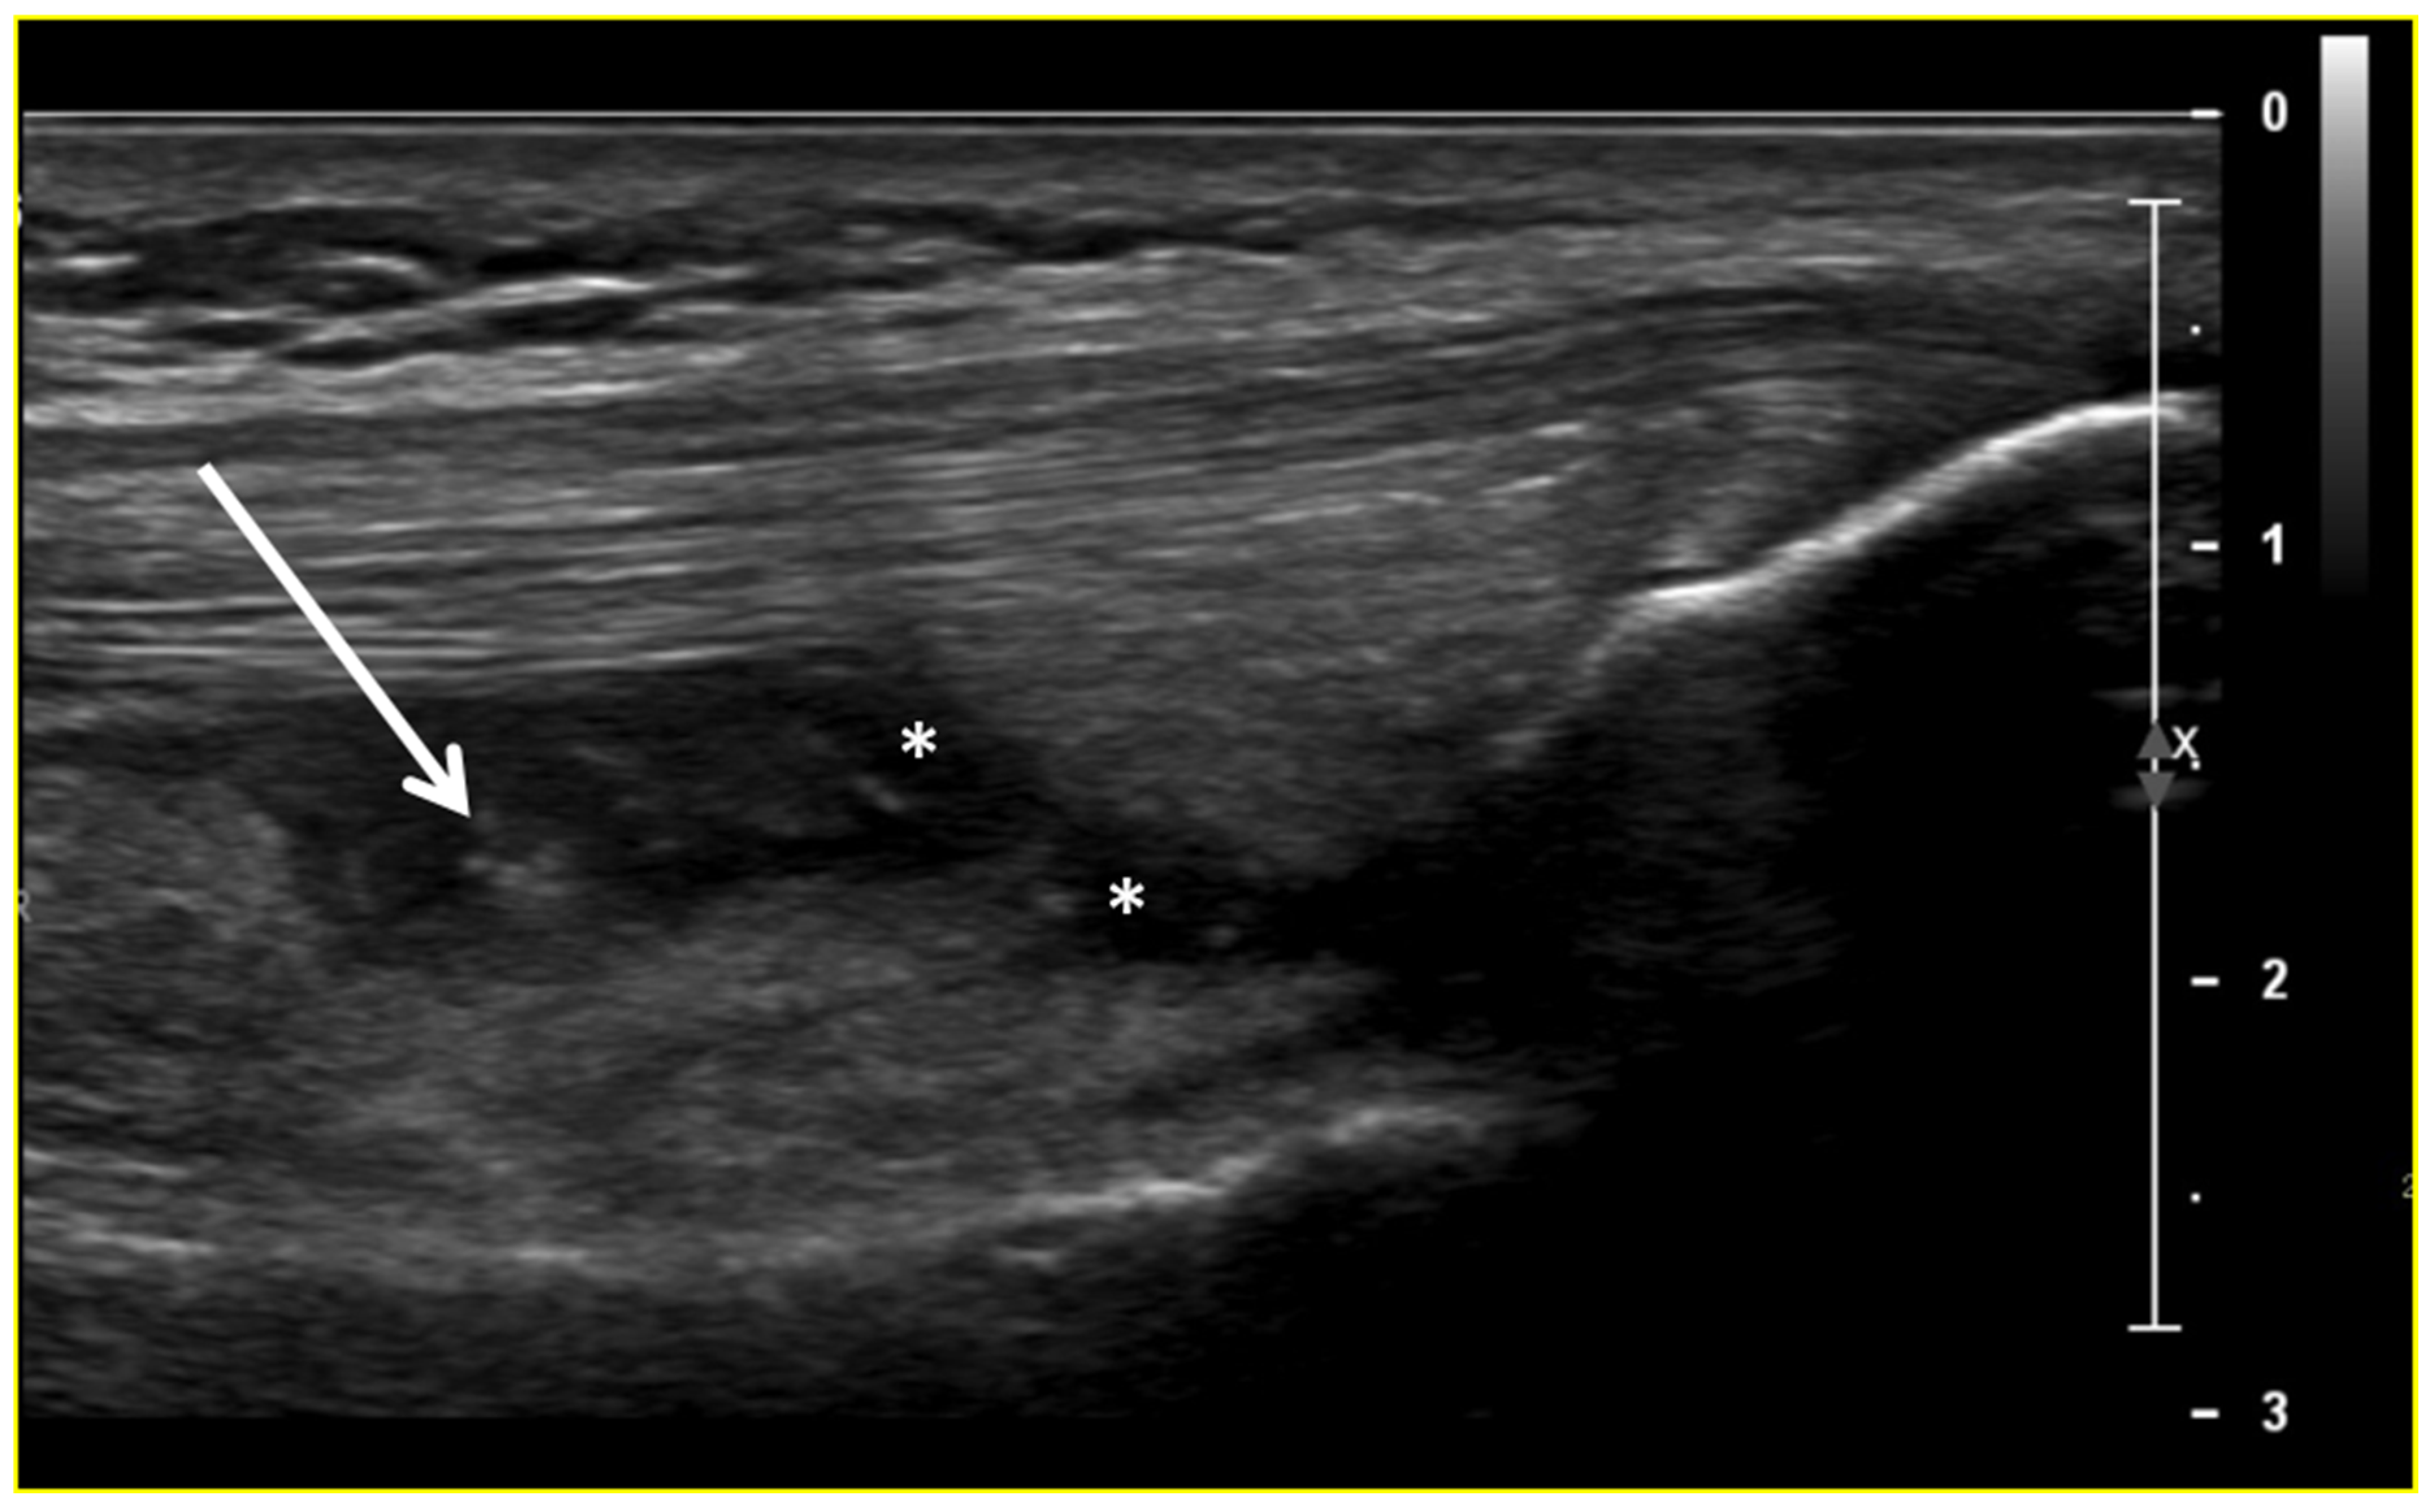

Ultrasound (US) imaging has not traditionally been used as part of the clinical pipeline for OA diagnostics. However, when examining the scientific literature, its role has risen steadily during the last two decades. US assessment of joints offers several advantages, including the ability to assess soft-tissue changes associated with OA and to outline the contour of the bony surface surrounding the joint [64,65]. In addition to detecting structural OA changes, a US can provide insights into inflammatory findings, complementing traditional CR imaging [66]. Several inflammatory findings (e.g., joint effusion/Baker cyst, synovial thickening, and hyper-vascularity), easily detectable throughout a US, are associated with pain exacerbation and disease progression in knee OA (Figure 2, Figure 3 and Figure 4).

Figure 2.

Ultrasound image (B-mode) longitudinal suprapatellar view showing joint effusion (asterisks) and synovial inflammatory thickening (arrow) within the sub-quadricipital recess.